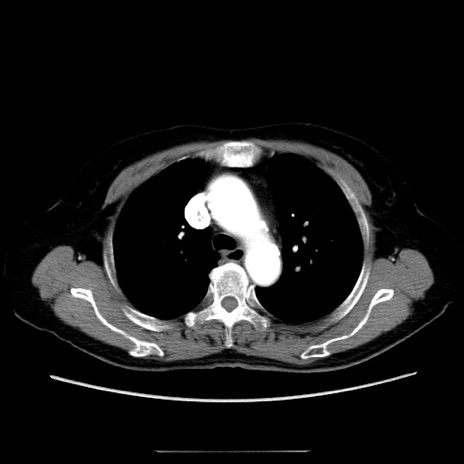

症例5(横断像)

【症例】70歳代女性

【主訴】お腹が張る

【現病歴】1週間くらい前から腹部膨満の自覚あり。昨日夜から増悪したため、本日救急外来受診。

【身体所見】意識清明、BT 36.5℃、BP 165/106mmHg、HR 80bpm、SpO2 98%、腹部:膨満、軟、自発痛・圧痛なし、触診にて不快感あり、腸蠕動音:減弱

【データ】WBC 12600、CRP 1.04